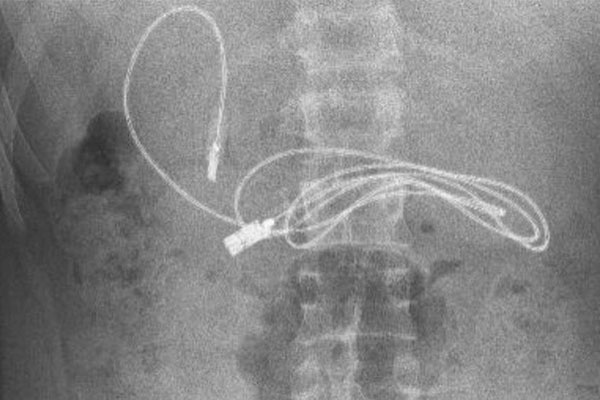

Sau khi chụp X-quang, bác sĩ phát hiện dạ dày của thiếu niên trên có một thiết bị bọc nhựa đang chờ tiêu hóa. Vì vậy, nhân viên y tế đã đưa bệnh nhân lên xe cấp cứu, chuyển đến Bệnh viện Đại học Firat ở Elazig (cách đó 3 giờ lái xe).

Tại Bệnh viện Đại học Firat ở Elazig, giáo sư Yasar Dogan - Trưởng khoa Tiêu hóa, Gan và Dinh dưỡng nhi - cùng đồng nghiệp đã thực hiện thủ thuật nội soi để loại bỏ dị vật trong dạ dày của bệnh nhân này.

Ngoài sợi dây sạc dài gần 1 mét, các bác sĩ còn lấy ra khỏi dạ dày của bệnh nhân 15 tuổi một dây buộc tóc.

"Chúng tôi đã gặp khó khăn trong việc tháo dây sạc ra, vì một đầu của dây đã đi vào ruột non. Sau khi ca phẫu thuật kết thúc thành công, bệnh nhân đã xuất viện trong tình trạng sức khỏe tốt", bác sĩ Dogan nói.